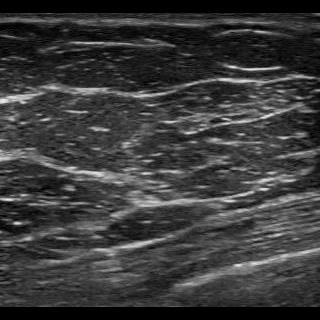

Deep learning has achieved promising results assessing different types of medical images [1]. However, for safe deployment and trustworthiness, the algorithms have to be able to tell when they cannot make proper assessments. This includes detecting out-of-distribution (OOD) data, which comprise data samples that the algorithm has not learned how to interpret. A lot of progress has been made in this area in recent years with numerous methods having been suggested for OOD detection [2] and uncertainty quantification [3]. In this study we explore different methods for OOD detection, including uncertainty-based ones, with the aim of being used in a tool for breast cancer classification in point-of-care ultrasound (POCUS) images. Breast cancer is the most common type of cancer amongst women worldwide [4]. Detecting breast cancer in an early stage improves patient outcome both in terms of mortality and morbidity, but access to diagnostics is lacking in many low- and middle-income countries [5, 6]. A possible solution could be a deep learning-based algorithm analyzing images captured with a POCUS device and using a smart-phone for visualization. Examples of POCUS images capturing breast tissue are shown in Fig. 1. In a previous study it has been shown that a convolutional neural network (CNN) can classify breast cancer in POCUS images with good performance [7]. Here we extend this work by exploring and evaluating three different OOD detection methods: softmax, energy score and deep ensembles. This should enable detecting unsuitable images during inference, which is crucial to make reliable assessments in a real world setting.

The ID data consists of POCUS images capturing breast tissue collected with a GE Vscan air probe [13] at Skåne University Hospital, Malmö. This data set contains images of normal tissue as well as benign and malignant lesions, see Fig. 1. The data was split into training and test set. In addition to the POCUS training set, a conventional ultrasound (US) data set of breast tissue was also used for training. These images were collected with Logiq E9 and Logiq E10 ultrasound machines at Skåne university hospital, Malmö. The sizes of the ID data sets are shown in Table 1.